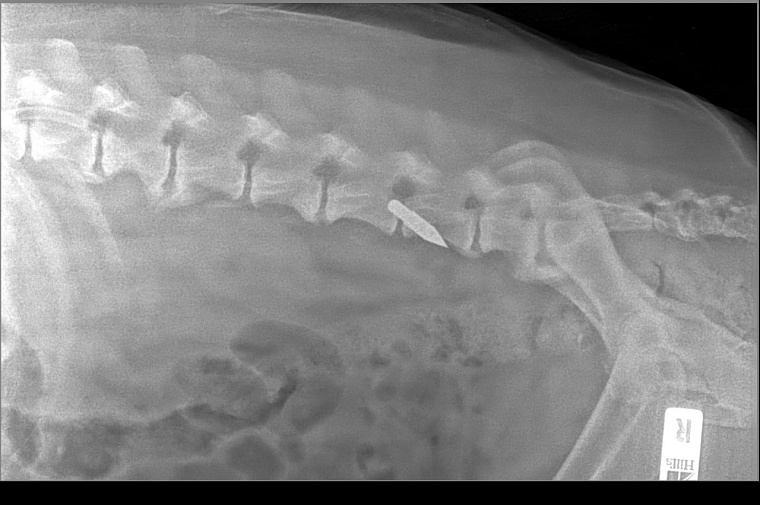

Напомним, раненого пса нашли поздно вечером 22 февраля в районе ММС в луже крови. Животное было ослаблено и переохлаждено. И хотя жизненно важные органы не были задеты и помощь подоспела, 10-летний пес не справился.

Фото: страница фонда "Потеряшки" в ВК